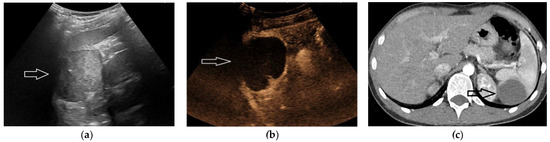

2.5. Hematoma and Abscess

2.6. Infarcts

2.7. Solid Lesions